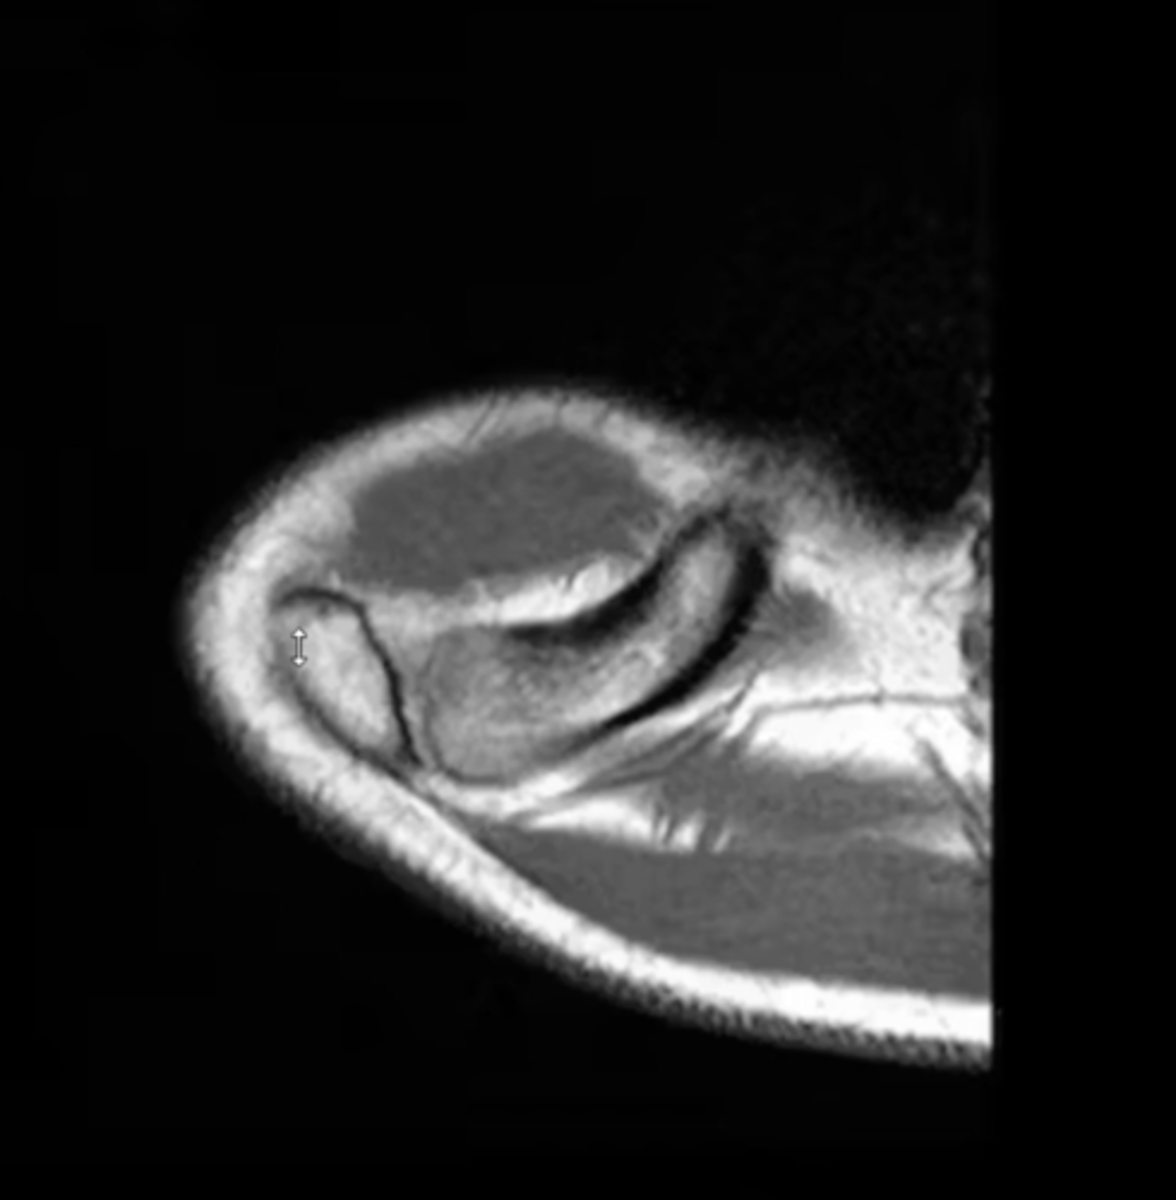

Rotator cuff tendinopathy -- image involves signal changes but the tendon is NOT yet torn

What is this image depicting w/ the rotator cuff? How do you know?